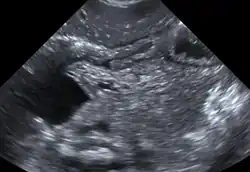

Bei Ultraschalluntersuchungen (vorgeburtlich im Rahmen von Pränataldiagnostik) fällt eine Duodenalatresie durch das sogenannte „Double-bubble-Phänomen“ auf: Der Magen des ungeborenen Kindes ist mit Flüssigkeit gefüllt (erste Blase / „Bubble“) und auch das Duodenum (Zwölffingerdarm) weist Flüssigkeit auf (zweite Blase / „Bubble“). Nebeneinander liegend zeigt sich aufgrund dessen im Ultraschall das Bild einer Doppel-Blase (sog. Double-Bubble).[2][3]

- ↑ Sonografie Abbildung 1 ( vom 21. Dezember 2012 im Internet Archive)

- ↑ Sonografie Abbildung 2